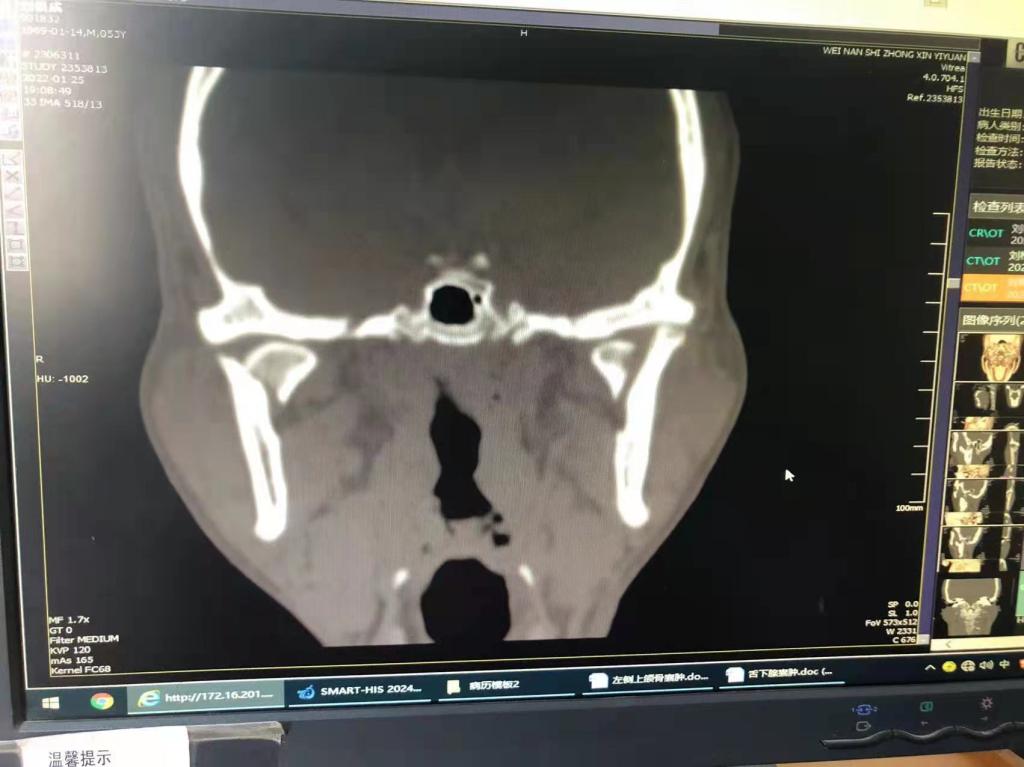

据了解,53岁的患者刘先生在1月25日当天走路不慎摔倒致下颌损伤,造成颏部软组织裂伤和张口困难,前往当地卫生院进行颏部裂伤清创缝合术。术后辗转到乐鱼在线登录入口口腔科门诊就诊,并进行颌面部CT检查提示为下颌颏部正中和双侧髁状突骨折,双侧下颌升支高度不一致,右侧较左侧变短1cm,张口重度困难,咬合关系错乱。刘先生因考虑在春节过后再入院治疗,于2月8日再次前来口腔科以“下颌骨骨折”收治人院。

口腔科主治医师蔺非非为患者入院后进行完善术前常规检查和颌间牵引恢复咬合关系。科主任李瑞春结合患者实际病情和检查结果认为,患者的髁突骨折在下颌骨骨折中所占比例较高,约为17.0%-36.3%。髁突骨折时,耳前区有明显的疼痛,局部肿胀、压痛。通过手指深入外耳道或在髁突部触诊,如张口时髁突运动消失,可能有骨折段移位。双侧低位骨折时,2个髁突均被翼外肌拉向前内方,双侧下颌支被拉向上方,可出现后牙早接触,前牙开秴。髁状突骨折易引起下颌后缩,张口困难,咬合关系错乱,关节强直等并发症。考虑患者系陈旧性骨折应尽早实施手术,避免骨折导致的张口困难、关节强直等并发症。因患者已经错过最佳治疗时期,决定尽快为患者进行手术治疗。

科主任李瑞春和主治医师蔺非非经过缜密的术前讨论和充分评估,手术在全身麻醉下进行,术中克服术野狭小操作不便困难,将下颌骨骨折完好对位,顺利地完成了"双侧髁状突和下颌颏部正中骨折切开复位内固定术"。术后检查患者面部对称,双侧下颌升支高度一致,咬合关系已恢复。